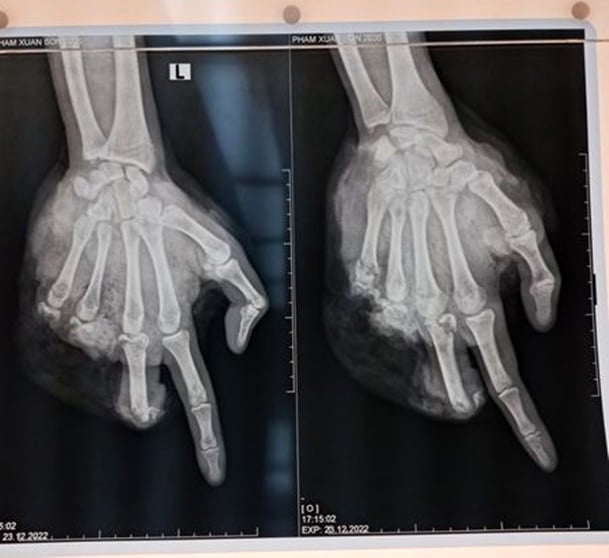

Một thiếu niên 16 tuổi ở Bắc Giang nhập viện trong tình trạng vết thương bàn tay trái phức tạp. Theo lời kể của gia đình, bệnh nhân lên mạng đặt mua pháo về rồi lấy thuốc pháo ra để chế thành các loại pháo có kích cỡ lớn hơn, nhiều thuốc nổ hơn. Sau đó, em này đem pháo đốt, tưởng pháo không nổ nên đã cầm lên. Lúc này, quả pháo bất ngờ phát nổ gây nát bàn tay trái, chân phải bị chấn thương nhẹ.

Bệnh nhân được đưa đến bệnh viện tuyến trước để được cầm máu, sau đó được chuyển đến Bệnh viện 108.

Tương tự, bệnh nhân nam, 15 tuổi, người Nam Định, cũng nghịch pháo tự chế; pháo nổ khiến em này bị nát bàn tay phải, gãy đốt 1 ngón tay phải, vết thương chảy máu phức tạp, bờ nham nhở, lộ gân cơ.

Các bác sĩ tại Bệnh viện 108 tiến hành xử lý vết thương, phẫu thuật cắt lọc, chỉnh trục các ngón tay, găm đinh cố định, khâu định hướng vết thương. Sau phẫu thuật, cả hai bệnh nhân tỉnh táo và các ngón tay đã hồng ấm và dần hồi phục.